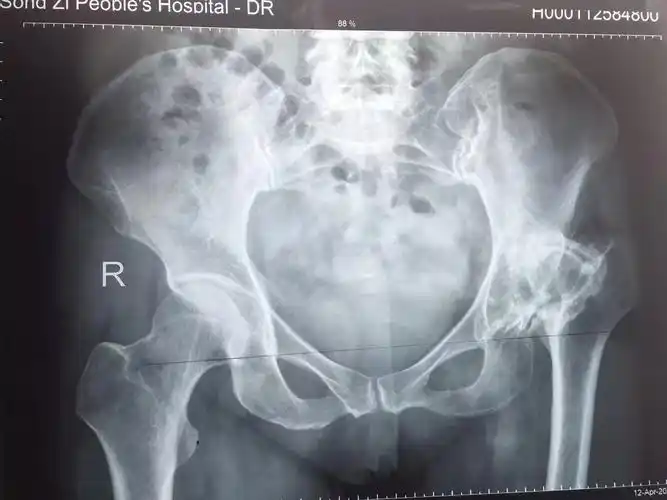

髋关节发育不良,随着孩子长大,能自己好转吗?

发育性髋关节发育不良

儿童发育性髋关节发育不良——易漏视但不容忽视的疾病

发育性髋关节发育不良ddh中老年人屁股疼痛的定时炸弹